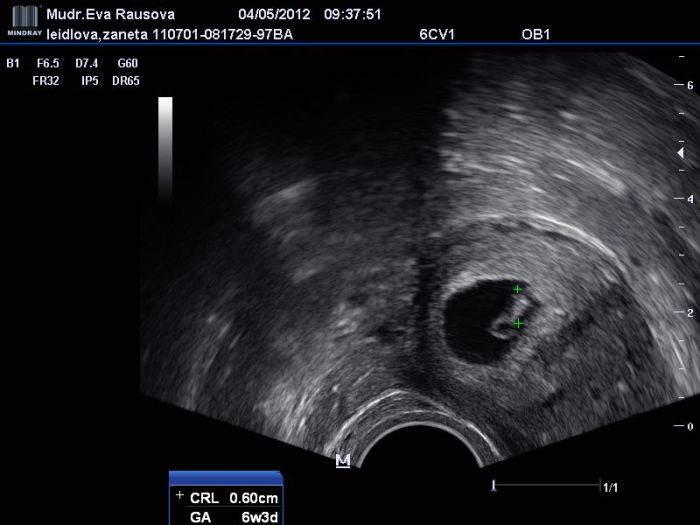

dávám zde fotečku, ale myšlím, že je na chlup stejná jako ta tvá, foto z pozdějšího ult ještě nemám, tak dávám alespoň tu naší "plácačku na mouchy" jak jsme to s manželem nazvali